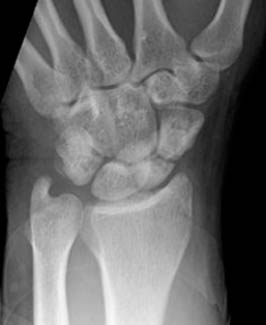

10) Name the abnormality shown in the image below.